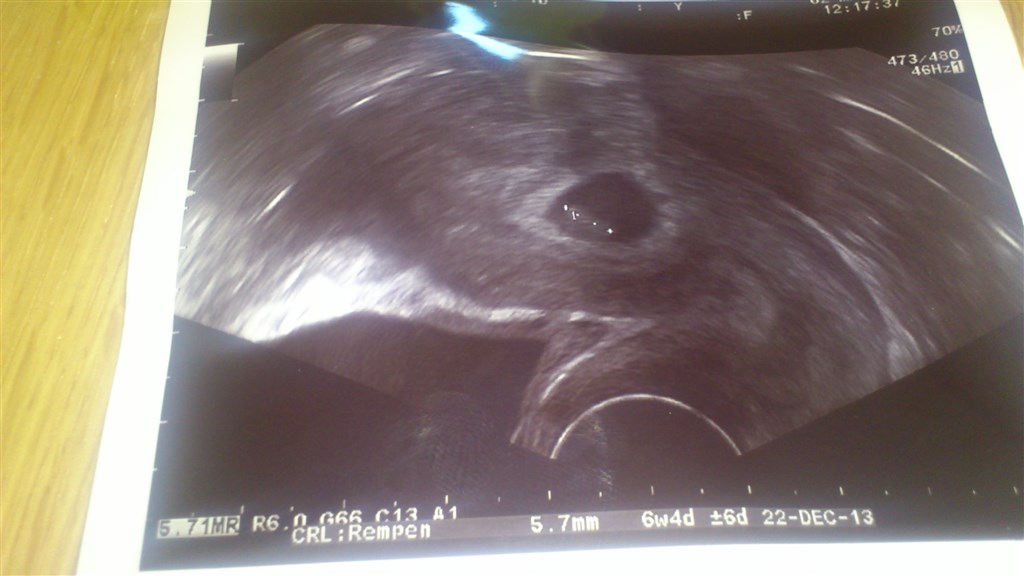

Vi er lige kommet hjem med en skumfidus i maven med et fint hoppende hjerte

Det er så fantastisk, men samtidig også så svært at forstå at det endelig er sket. Er så lykkelig

Vedhæftede fotos (klik for at se i fuld størrelse)